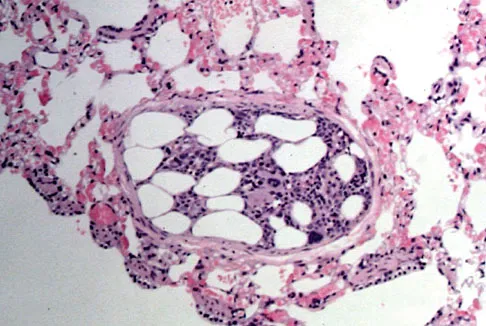

Figures 11a and 11b show the AP and lateral radiographs of a 32-year-old patient on hemodialysis who has increasing elbow pain and a visibly growing mass over the extensor surface. Figure 11c shows the photomicrograph of the biopsy specimen. What is the most likely diagnosis?

Explanation

The radiographic findings are classic for tumoral calcinosis; they are not consistent with myositis ossificans, fungal granuloma, or hemochromatosis. The condition typically appears as large aggregations of dense calcified lobules confined to the surrounding soft tissues. Hyperphosphatemia is a fundamental factor in many patients with this condition. Tumoral calcinosis also occurs in the setting of chronic renal failure when mineral homeostasis is not controlled. The histologic appearance is essentially a foreign body granuloma reaction. Multilocular cysts with purplish amorphous material are surrounded by thick connective tissue capsules. The fibrous walls contain numerous foreign body giant cells. Surgical excision is indicated if the tumor causes discomfort or interferes with function. Sisson HA, Murray RO, Kemp HBS (eds): Orthopaedic Diagnosis: Clinical, Radiological and Pathological Coordinates. New York, NY, Springer-Verlag, 1984.